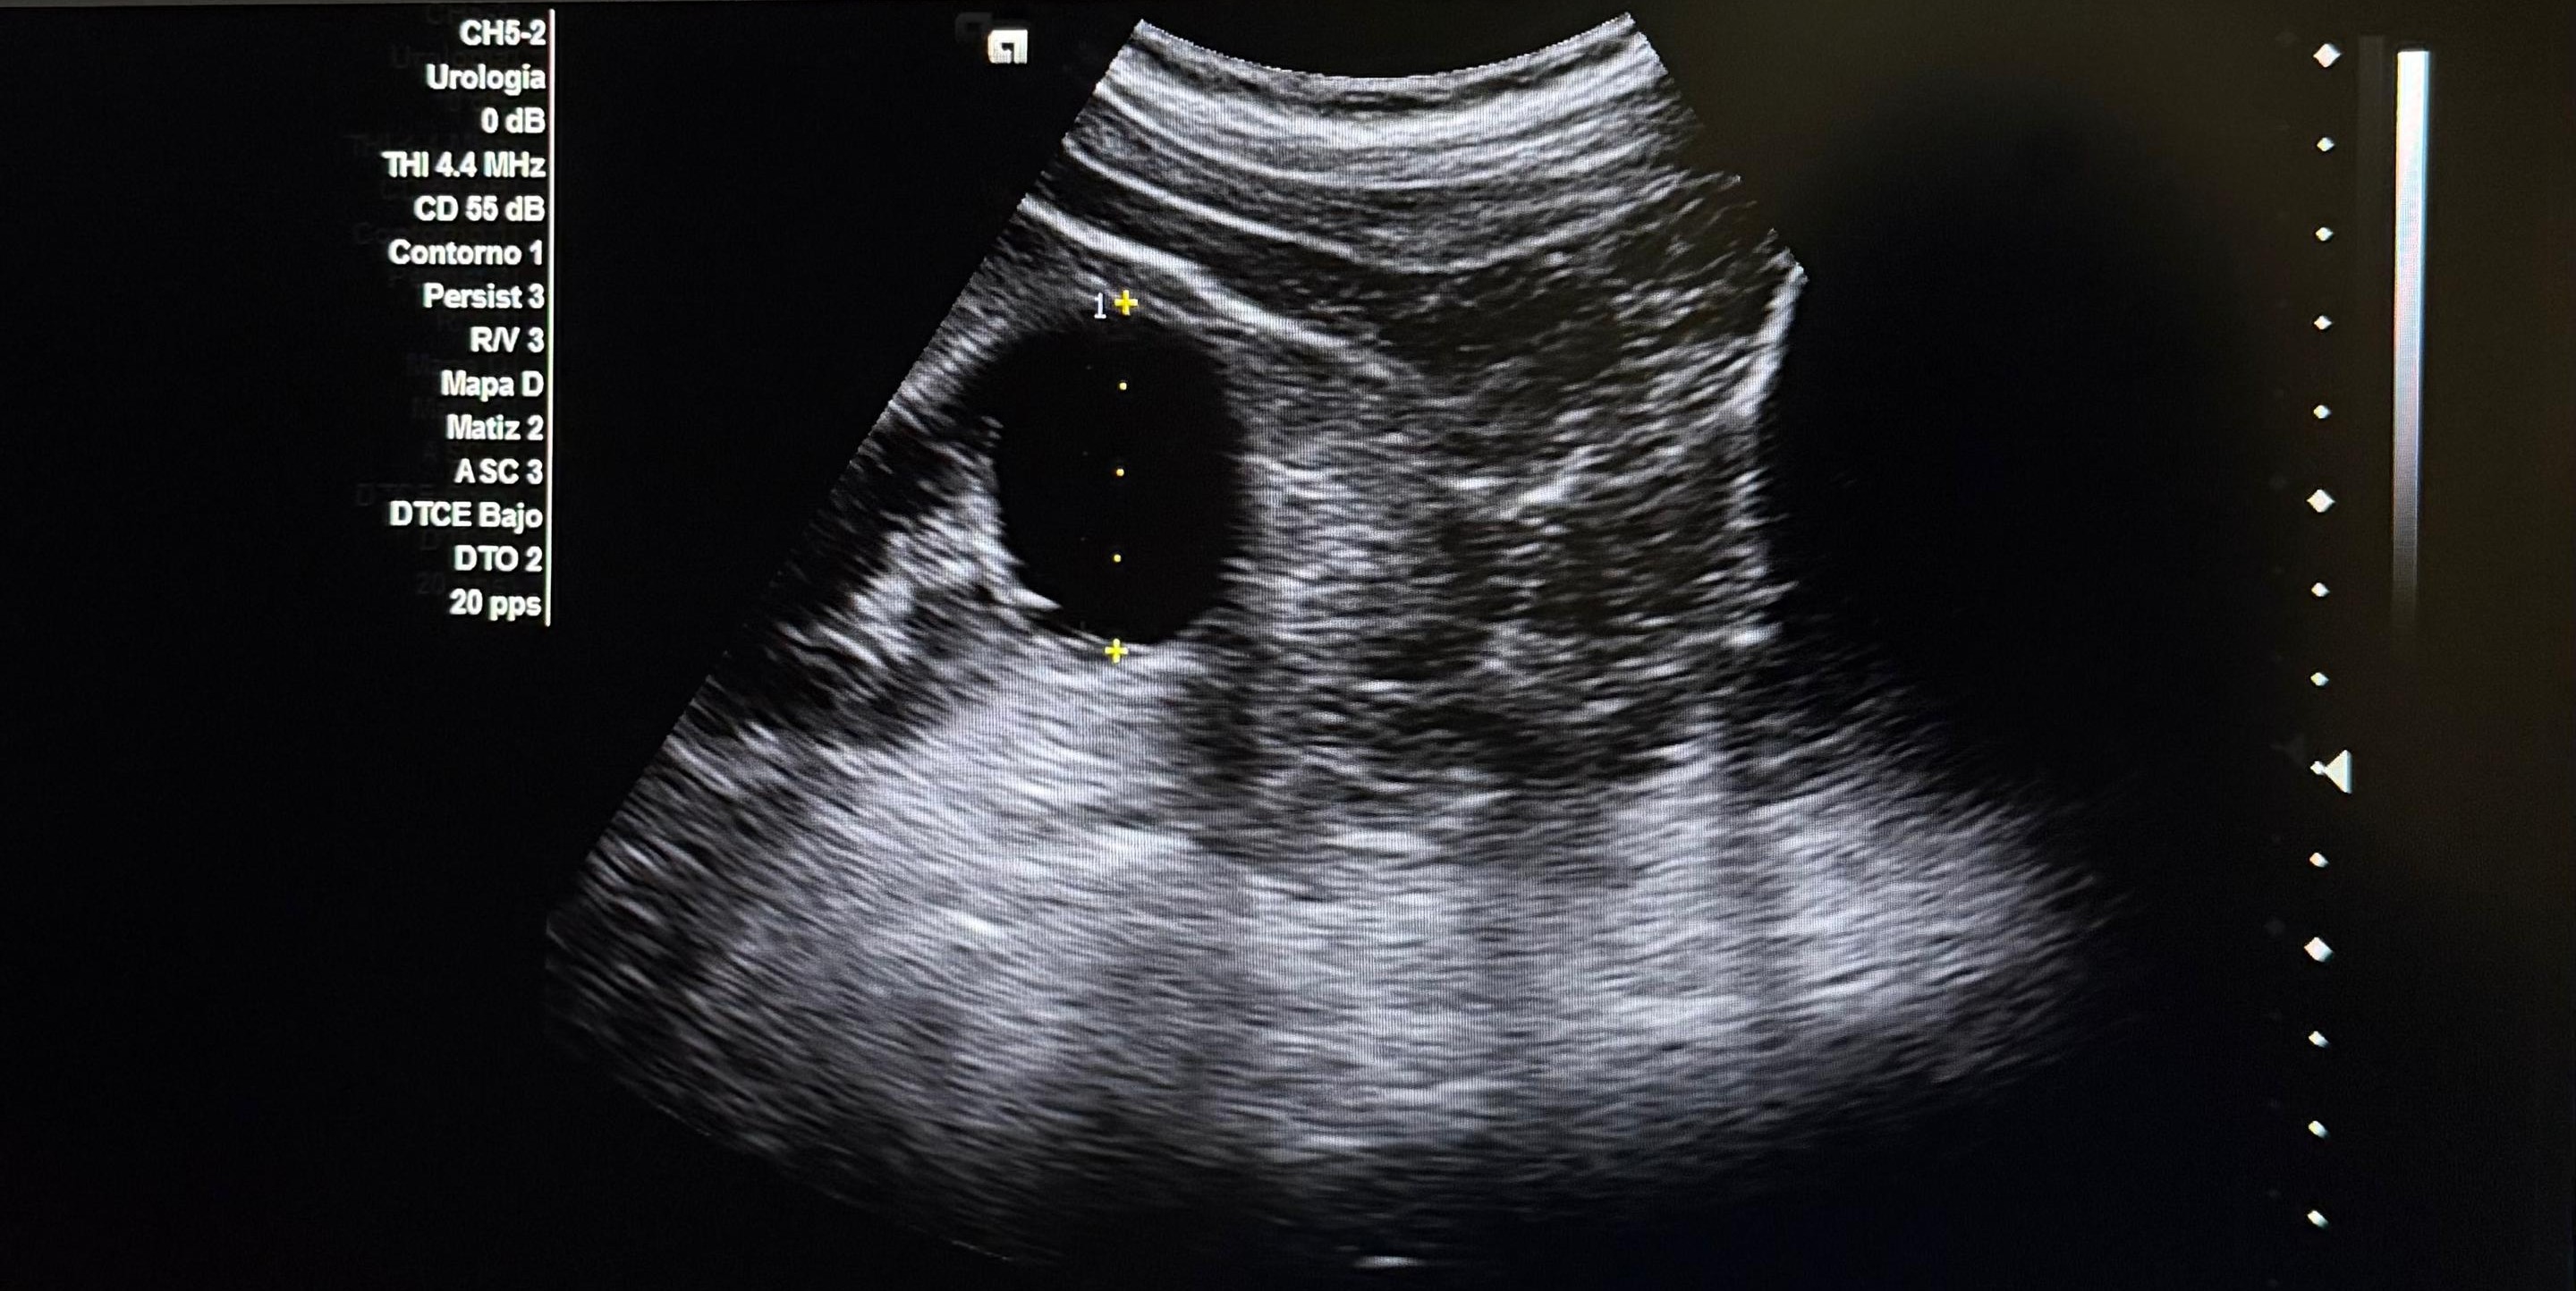

Hallazgos ecográficos

Se realiza ecografía abdominopélvica donde se visualiza vejiga sin alteraciones, próstata aumentada de tamaño con un volumen estimado de 59 cc. Como hallazgo incidental se objetivan ambos riñones aumentados de tamaño con varios quistes.

Juicio clínico: HBP y hallazgos compatibles con quistes simples vs poliquistosis renal.